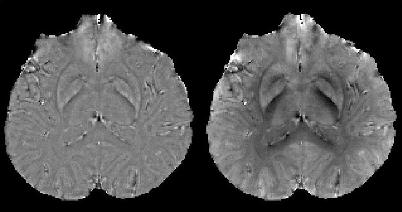

MRI에서 주 분극 B0장(field)을 따라 비강자성 생체 물질의 국부적인 는 감수율에 의해 유도되며, 이는 부피 감수율 분포 와 쌍극자 커널 의 컨볼루션이다: . 이 공간 컨볼루션은 푸리에 영역에서 점별 곱셈으로 표현될 수 있다.[6][7] . 이 푸리에 표현은 감수율 분포가 알려져 있을 때 필드 섭동을 예측하는 효율적인 방법을 제공한다. 그러나 필드에서 소스로의 역 문제는 푸리에 영역에서 B0에 대한 매직 각에서 한 쌍의 원뿔 표면에서 0으로 나누는 것을 포함한다. 결과적으로 감수율은 원뿔 표면의 공간 주파수에서 불확정되며, 이는 재구성된 QSM에서 심각한 줄무늬 인공물로 이어진다.

COSMOS는 여러 방향에서 과도한 샘플링을 통해 역 문제를 해결한다.[11][12] COSMOS는 푸리에 변환 영역에서 제로 콘 표면이 B0 필드에 대해 매직 각도로 고정되어 있다는 사실을 활용한다. 따라서 객체가 B0 필드에 대해 회전하면 객체의 프레임에서 B0 필드가 회전하고 콘도 회전한다. 결과적으로 콘으로 인해 계산할 수 없는 데이터는 새로운 방향에서 사용할 수 있게 된다.

COSMOS는 모델이 없는 자화율 분포를 가정하고 측정된 데이터에 대한 완전한 충실도를 유지한다. 이 방법은 ''생체 외'', ''생체 내'' 및 팬텀 실험에서 광범위하게 검증되었다. ''생체 내'' 인간 뇌 영상에서 얻은 정량적 자화율 맵 또한 뇌 해부학에 대한 이전 지식과 높은 수준의 일치를 보였다. COSMOS에는 일반적으로 세 가지 방향이 필요하므로 임상 적용의 실용성이 제한된다. 그러나 다른 기술을 보정할 수 있을 때 참조 표준 역할을 할 수 있다.

임계 k-공간 분할(TKD)[12][17]은 단일 각도 획득만 필요하며, 구현이 쉽고 계산 속도가 빠르다는 장점을 가지고 있다. 그러나 정량 감수성 지도화(QSM)에서는 줄무늬 인공물이 자주 나타나며, 감수성 값은 COSMOS로 계산된 QSM에 비해 과소평가된다.